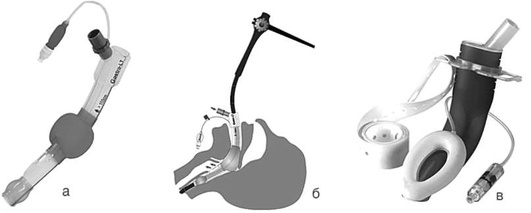

В качестве средства для временного обеспечения вентиляции, изоляции трахеобронхиального дерева (ТБД) от пищеварительного тракта и дренирования желудка могут быть использованы НВУ так называемого II поколения с дренирующим каналом [ларингеальные маски Supreme (рис. 2.34, а), безманжеточное НВУ I-Gel (рис. 2.34, б), НВУ LTS-D (рис. 2.34, в), НВУ LMA Protector (рис. 2.34, г) и др.]. Все эти устройства снабжены каналом для дренирования желудка, однако не позволяют выполнение интубации трахеи через них вслепую. При наличии навыка и оснащения возможно выполнение интубации трахеи в один этап с помощью гибкого интубационного эндоскопа через ряд НВУ II поколения (например, LMAProtector) либо использование трубкообменника на гибком эндоскопе с последующим извлечением НВУ, слепым заведением эндотрахеальной трубки (ЭТТ) по трубкообменнику в трахею и извлечением трубкообменника (например, Supreme, LTS-D).

pic 0043

Рис. 2.34. Надгортанное воздуховодное устройство II поколения: а - ларингеальная маска Supreme, Teleflex Medical; б - безманжеточное надгортанное воздуховодное устройство I-Gel, Intersurgical; в - LTS-D, VBM; г - LMA Protector, Teleflex Medical

В случае необходимости выполнения неинтубированным пациентам в ОРИТ длительной фиброгастродуоденоскопии могут возникнуть показания к седации для снижения дискомфорта во время процедуры. Пациенты в критическом состоянии в значительной части случаев характеризуются парезом кишечника, нарушениями эвакуаторной функции желудка, и длительная седация в условиях спонтанного дыхания потенциально опасна гипоксемией, аспирацией. Для обеспечения безопасности пациентов в ОРИТ возможно применение специально разработанных НВУ, обеспечивающих вентиляцию, защиту от аспирации, свободный пассаж гастродуоденоскопа через выделенный канал в пищевод (рис. 2.40). Данная методика позволяет безопасно провести эндоскопические исследования и вмешательства на верхнем отделе ЖКТ без риска гипоксемии, аспирации и необходимости выполнения кратковременной интубации трахеи.

pic 0049

Рис. 2.40. Специальные надгортанные воздуховодные устройства для выполнения эндоскопических исследований верхних отделов желудочно-кишечного тракта: а - Gastro-Laryngeal Tube (G-LT, VBM); б - схема выполнения фиброгастродуоденоскопии (ФГДС) через G-LT; в - LMA® Gastro? Airway, Teleflex Medical